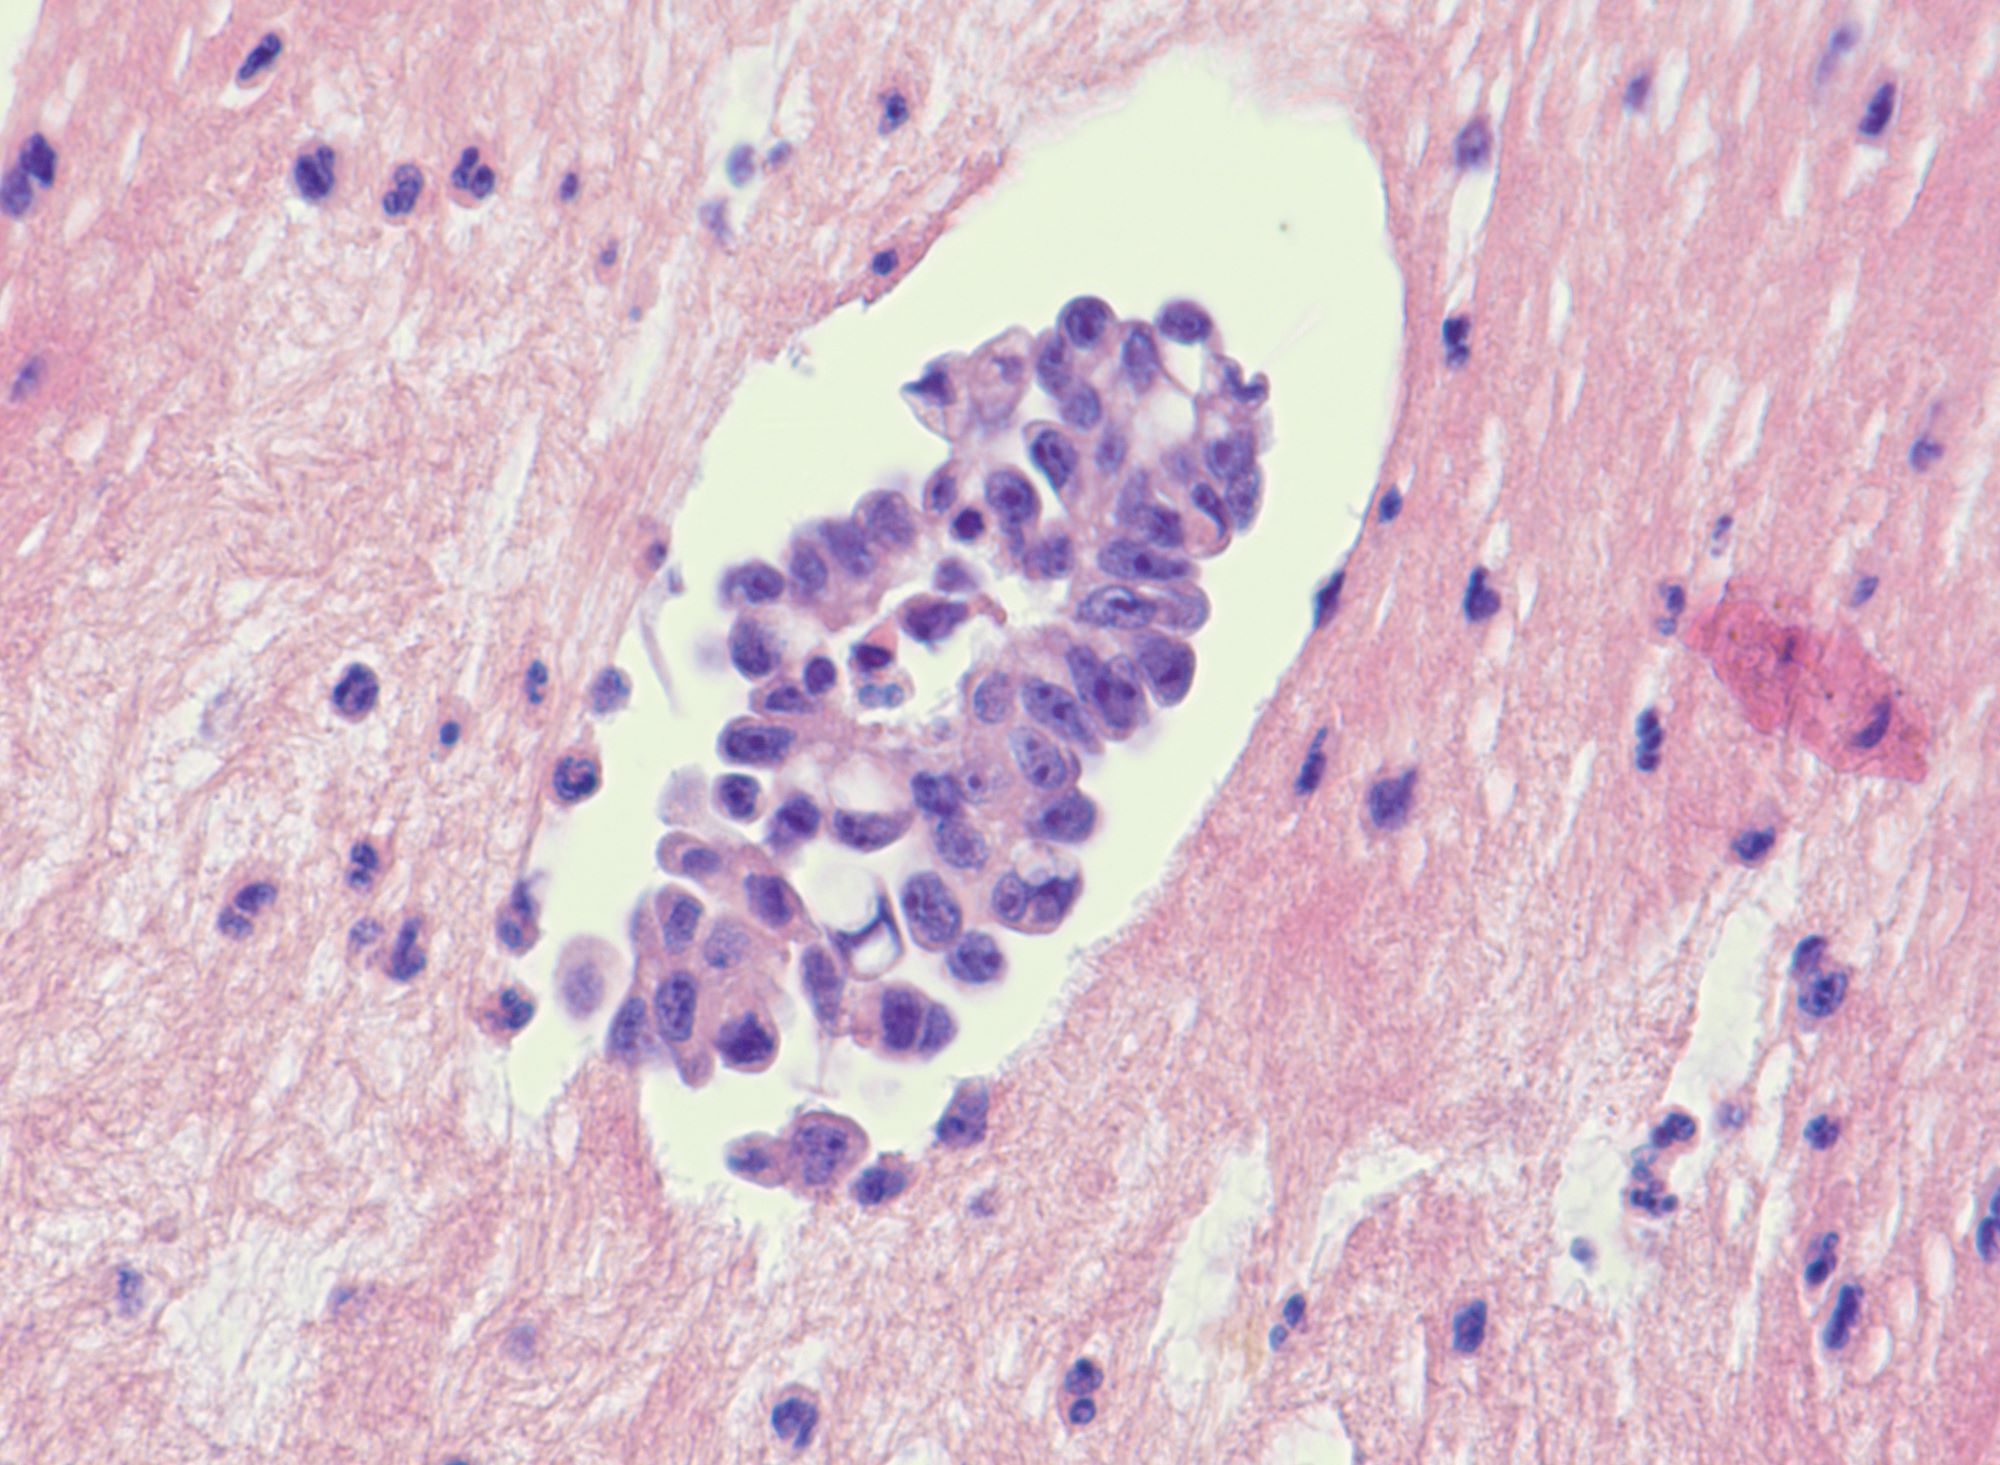

Microscopic (histologic) description

- Uniform / homogeneous population of small cells with scant cytoplasm

- Mild to moderate nuclear atypia at most (grade 1 or 2)

- No nuclear pleomorphism (< 3x variation in size) (Hum Pathol 2005;36:1049)

- May have a conspicuous nucleolus

- Low mitotic index: < 12 mitotic figures per 10 high power fields

- Little to no necrosis

- Psammoma bodies are frequent

- 2 patterns, noninvasive and invasive:

- Noninvasive: nonhierarchical architecture with micropapillary or cribriform patterns with significant expansile growth

- Invasive (> 5 mm): micropapillary or complex papillae, compact cell nests, inverted macropapillae (with broad fibrovascular cores), cribriform, glandular or cystic, solid sheets with slit-like spaces and single cells

- Multiple different invasive patterns can exist within one tumor

Microscopic (histologic) images